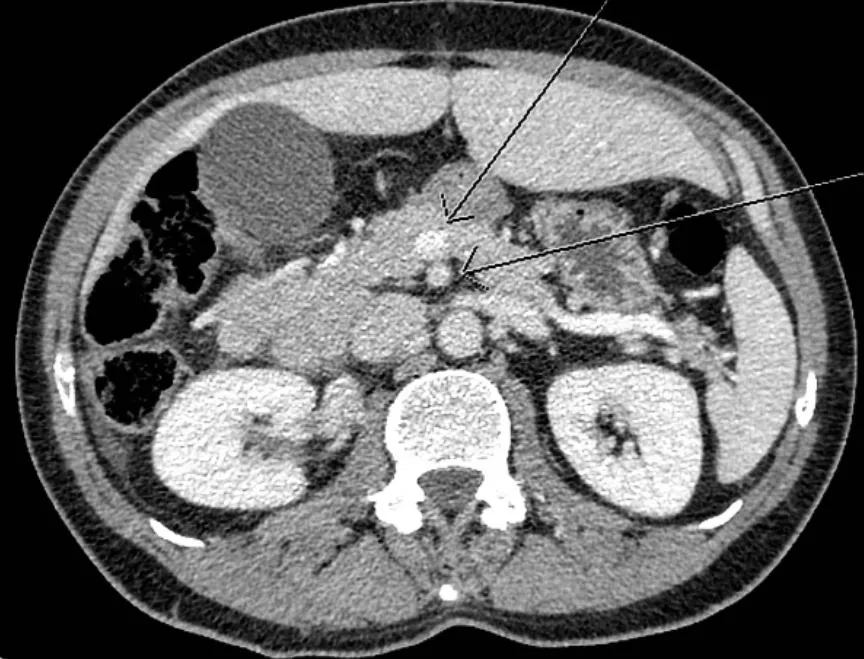

운동안하고 기름진 음식 먹으면 이렇게 혈관이 막힙니다

CT판독은 저도 잘 못합니다... 장이 꼬였대요

외래에서 갈등의 요소가 된 것 중에 하나가 수술을 해야하나 말아야 하나 때문인데, 아마 이 상황은 아이의 장이 꼬여서 괴사가 진행된 경우인 듯 하다.

보통 장이 꼬여도 저절로 풀리는 경우가 많아서 괴사가 진행되지 않으면 기다려볼 수 있겠으나 이미 괴사가 진행됐다면 수술을 해야한다. 안 그러면 터진다...